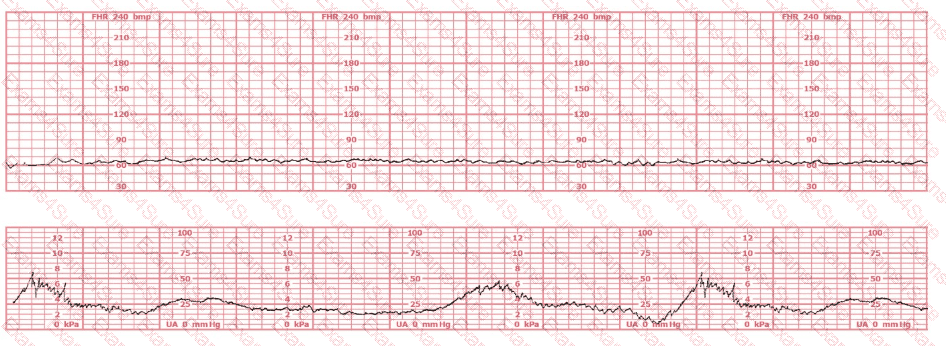

The fetal heart rate tracing shown is obtained upon the woman's admission to labor and delivery. This tracing is most consistent with what maternal condition?